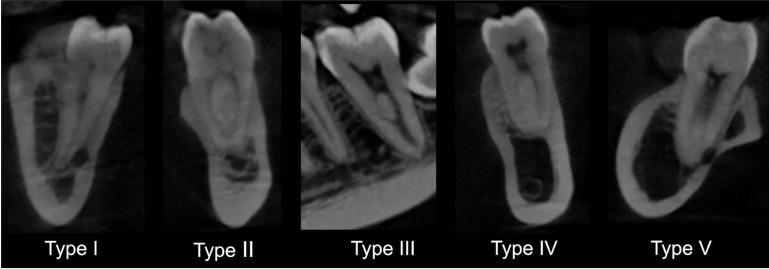

In total, 121 CBCT images of patients were selected from a database. All images contained lower first and second premolars and molars on both sides of the arch, fully developed roots, and no treatment, resorption, or calcifications. In each image, the root canals of the lower premolars and molars were evaluated according to the Vertucci classification in On-Demand 3D software in the multiplanar reconstruction with dynamic navigation. Twenty-five percent of the images were re-assessed to analyze intraobserver confidence with the kappa test. Data were statistically evaluated with linear regression to evaluate the correlations of anatomic variations with age and sex, and the Wilcoxon test to analyze the laterality of variations, with a significance level of 5%.

The intraobserver agreement (0.94) was excellent. In general, the root canals of lower premolars and molars showed a higher prevalence of type I than other Vertucci classification types, followed by type V in premolars and type II in molars. When the molar roots were evaluated separately, type II was more frequent in mesial roots and type I in distal roots. Although age showed no correlations with the results, sex and laterality showed correlations with tooth 45 and the lower second premolars, respectively.